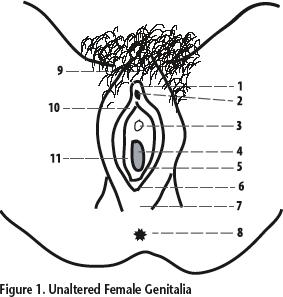

Clitoris

External urethral orifice (female)

Labia majora/minora

Prepuce (=clitoral hood)

Vaginal orifice

Vestibule (of vulva)